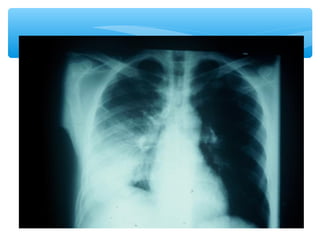

Radiografía

 Condensación en

lóbulo/s

Radiológico

Community acquired pneumonia (Streptococcus pneumoniae) (a) and (b): PA and

lateral chest films show consolidation in the lateral segment of the middle lobe,

abutting the major and minor fissures.

PA chest radiograph shows an alveolar consolidation involving the right and left lower

lobes in a patient infected by Streptococcus pneumoniae

Community acquired pneumonia(Streptococcus pneumoniae) (a) and (b): PA and lateral chest films show consolidation in the lateral segment of the middle lobe, abutting the major and minor fissures.

PA chest radiographshows an alveolar consolidation involving the right and left lower lobes in a patient infected by Streptococcus pneumoniae